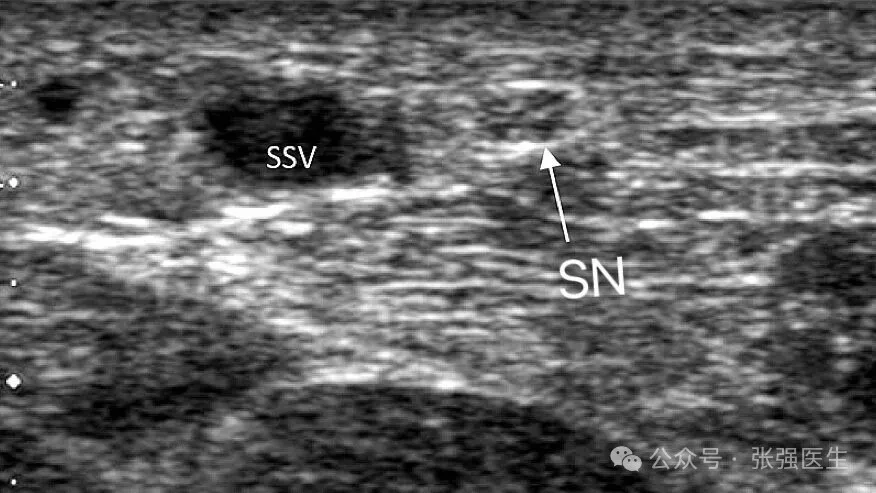

小隐静脉并不是一条孤立存在的血管,它与腓肠神经(sural nerve)伴行,在腘窝区域又与胫神经(tibial nerve)关系密切。

小隐静脉与腓肠神经在多数情况下的距离小于5 mm;在腘窝区(SPJ),与胫神经的平均距离约为4.4 mm,部分个体甚至小于1 mm;同时,在小腿远端约三分之二的区域,深筋膜常缺失或不连续,缺乏有效的解剖隔离。

这一系列结构特征共同决定了:在小隐静脉系统中,静脉与神经并非简单相邻,而是处于高度共存的状态。